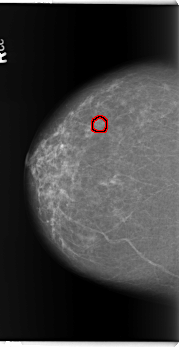

B_3362_1.RIGHT_CC

RIGHT_CC LINES 5896 PIXELS_PER_LINE 3040 BITS_PER_PIXEL 12 RESOLUTION 50 OVERLAY

FILE: B_3362_1.RIGHT_CC.OVERLAY

TOTAL_ABNORMALITIES 1

ABNORMALITY 1

LESION_TYPE CALCIFICATION TYPE ROUND_AND_REGULAR DISTRIBUTION CLUSTERED

LESION_TYPE MASS SHAPE IRREGULAR MARGINS MICROLOBULATED-ILL_DEFINED

ASSESSMENT 3

SUBTLETY 3

PATHOLOGY BENIGN

TOTAL_OUTLINES 1

BOUNDARY